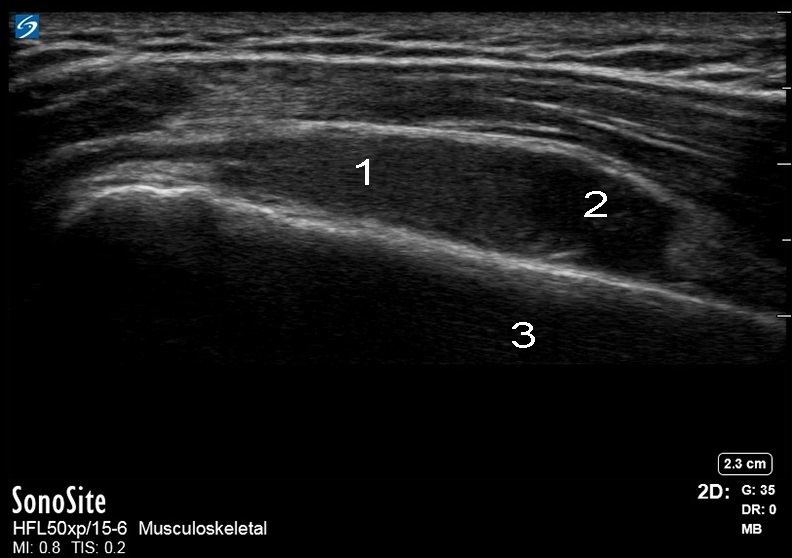

肩外側の肩峰下涙記号画像

滑液包

単純な流体

外側上腕骨 SX 首